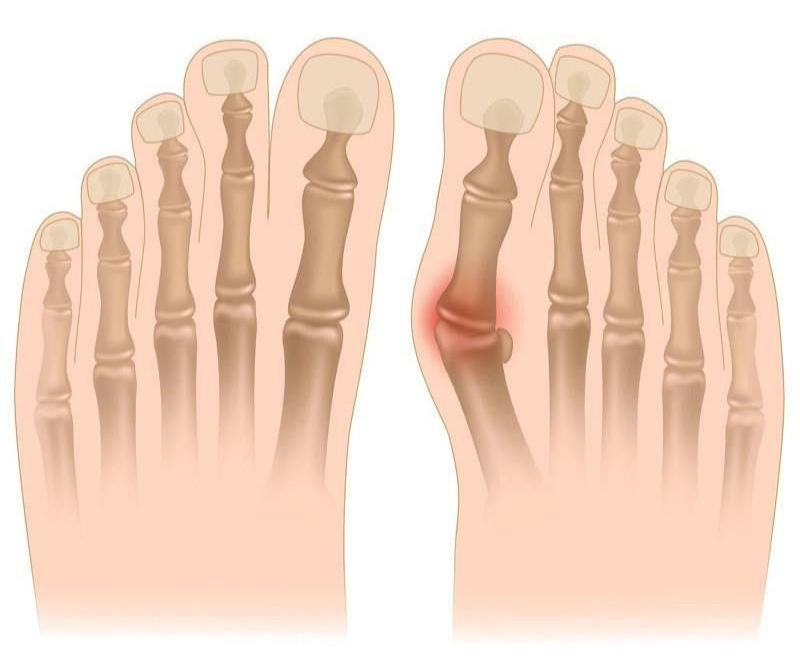

무지외반증 증상은 첫째, 엄지발가락이 휘고 둘째, 발 내측 부위에 통증이 있으며 셋째, 통증 부위가 붉은색을 띄고 넷째, 엄지발가락을 제외한 나머지 발가락들이 저릴 수 있으며 다섯째, 제대로 걷기 힘들다 등으로 요약해볼 수 있는데요. 아래와 같이 무지외반증 증상을 네 단계로 나누어볼 수도 있어요.

4단계: 변형된 엄지발가락이 두 번째 발가락과 겹쳐지는 교차변형이 생기고 인접한 다른 발가락에도 통증이 생김.